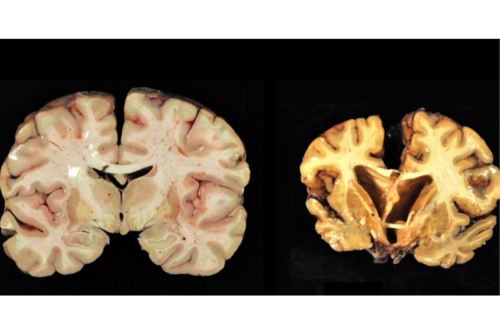

Estas lesiones dentro del Fútbol Americano podrían provocar una afección llamada encefalopatía traumática crónica o CTE, un problema grave para los deportistas, además puede provocar demencia en el futuro e incluso la muerte prematura.

El equipo de los Institutos Nacionales de Salud por sus siglas en ingles NIH, estimaron la cantidad y los tipos de impactos en la cabeza en los jugadores y compararon los datos con diagnósticos de CTE de más de 600 exjugadores de fútbol americano y se llegó a la conclusión de que el riesgo de sufrir CTE varía según el nivel más alto de juego de la persona, y que el riesgo de CTE aumentó un 15 %.